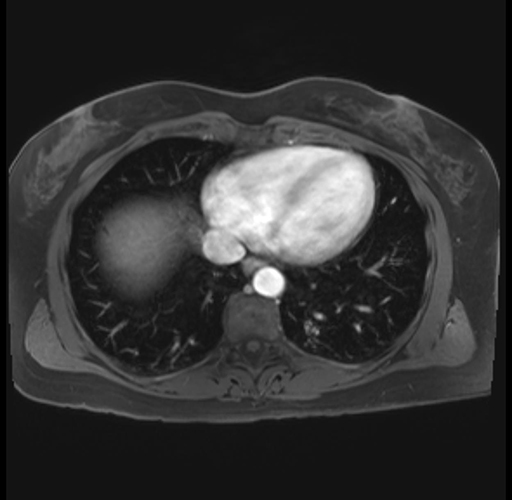

Imaging Analysis

Look through the patient's CT scan to identify any areas of concern for the necessary procedure.

Based on your CT findings, which issue(s) are present and would give reason for "planned slowing down moment(s)" in this case?

Considering a standard distal pancreatectomy procedure, what step(s) of the operation would you do differently in this case?